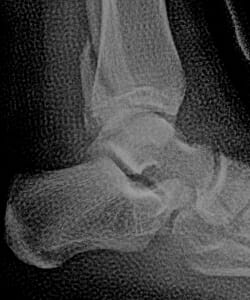

Abb. 1:

Röntgenbild eines Sprunggelenkverrenkungsbruches – innen vergrößerte Distanz zwischen Innenseite des Innenknöchels und Sprungbein